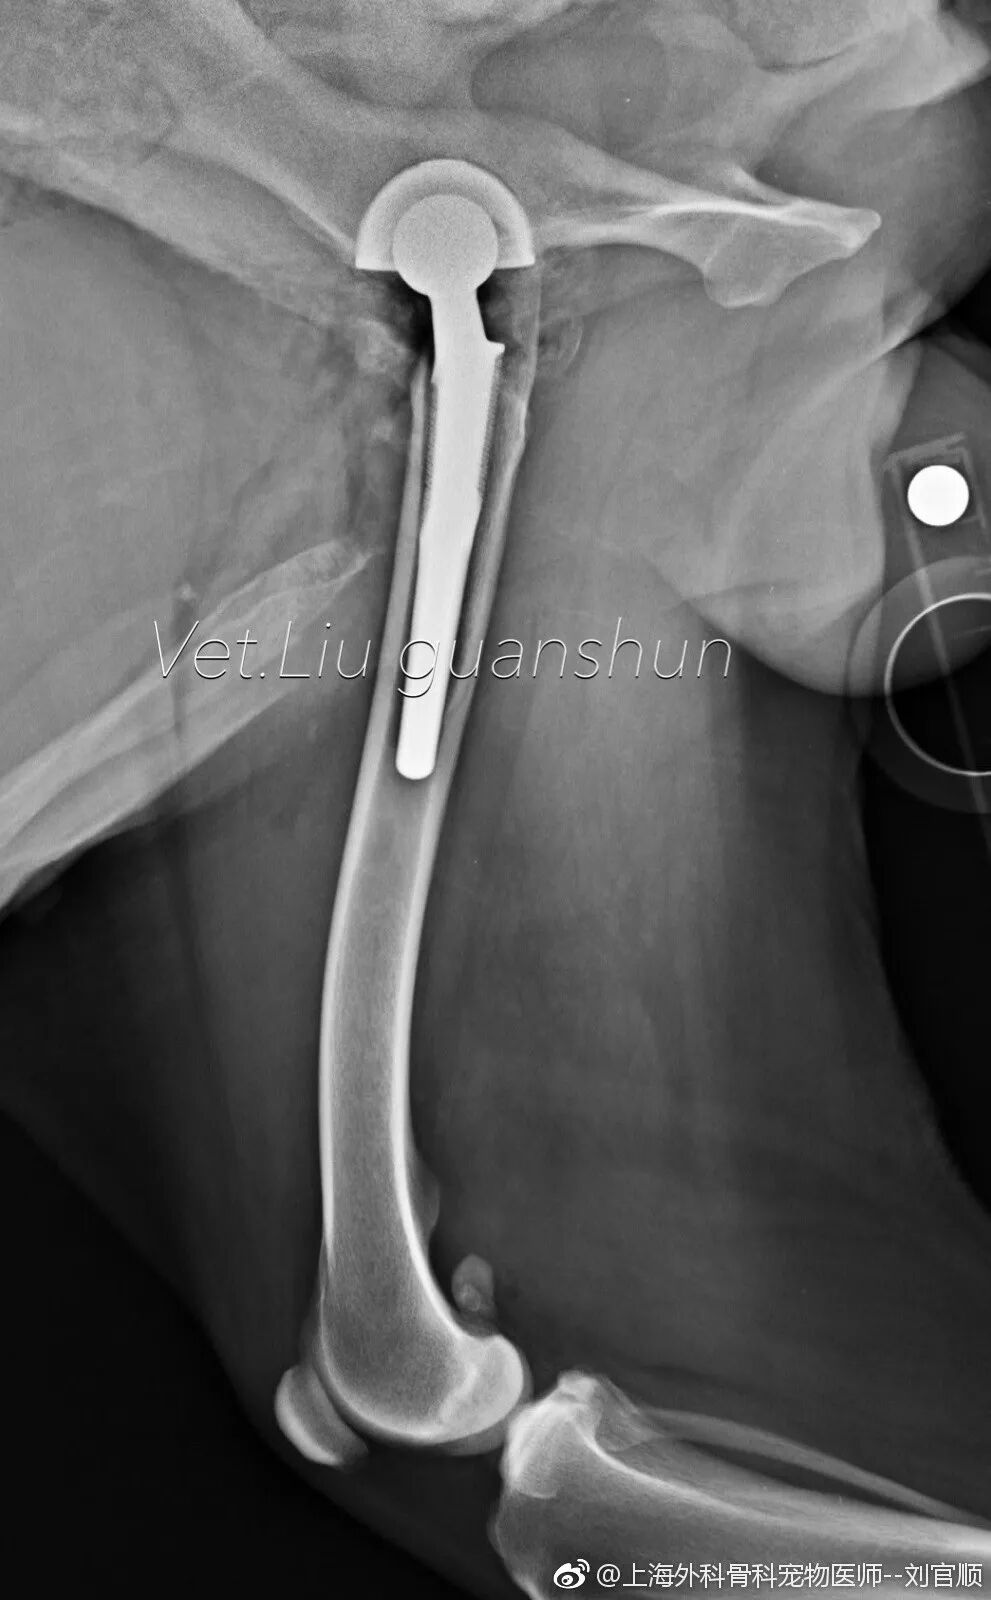

外科专科、骨科专科、心脏病门诊、髋关节置换、前十字韧带手术等

髋关节置换手术后第三天,出来活动活动!

中国取得BioMedtrix全髋置换全部认证的只有两位兽医师